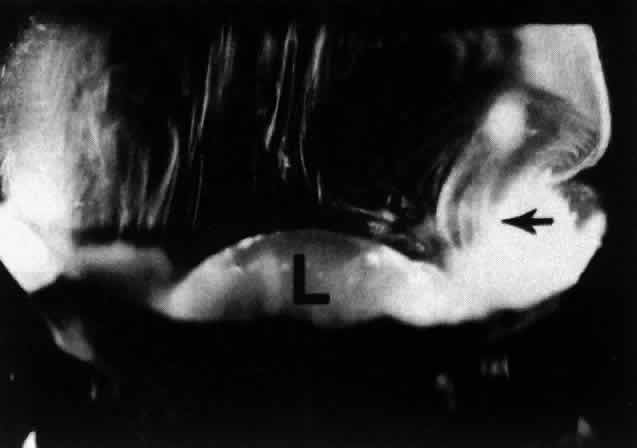

During childhood only the vitreous cortex scatters incident light and thus appears dense (Fig. 9). There are no visible fibers within the corpus vitreous until middle age (see Figs. 4 THROUGH 6). During old age these fibers become thickened and tortuous, associated with many pockets of liquid vitreous and a collapsed (syneretic) appearance (Fig. 10). These changes are the result of age-related biochemical alterations in the composition and organization of the molecular components that simultaneously result in vitreous liquefaction and fiber formation. Pockets of liquid vitreous have classically been called “lacunae.” In addition to having a low density of collagen during youth, the central vitreous is the first region to undergo liquefaction during middle age.16 A report by Kishi and Shimizu18 described the presence of a “posterior vitreous pocket” that the authors interpreted to represent an anatomic entity. However, over 95% of the eyes examined in that study were from persons aged 65 years or older. Thus, these findings represent the result of age-related vitreous liquefaction in the central precortical posterior vitreous.93 Such changes could also explain the preferential pooling of aqueous dyes such as India ink17 placed onto the anterior vitreous and allowed to collect anterior to the macula in what appears as a “bursa.”17,94,95 The use of fluorescein by Kishi and Shimizu18 represents but another way of demonstrating the phenomenon of vitreous liquefaction in this region.

Fig. 9. This view of the posterior and central vitreous from a 4-year-old child demonstrates a dense vitreous cortex (arrows) with hyalocytes (small retractile “spots” in cortex) and no intravitreal fibrous structures. The lens (L) is seen below.